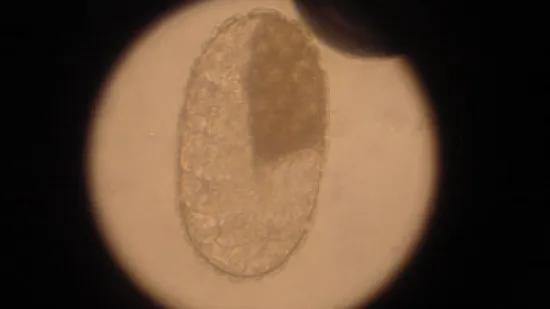

Photo de la semaine